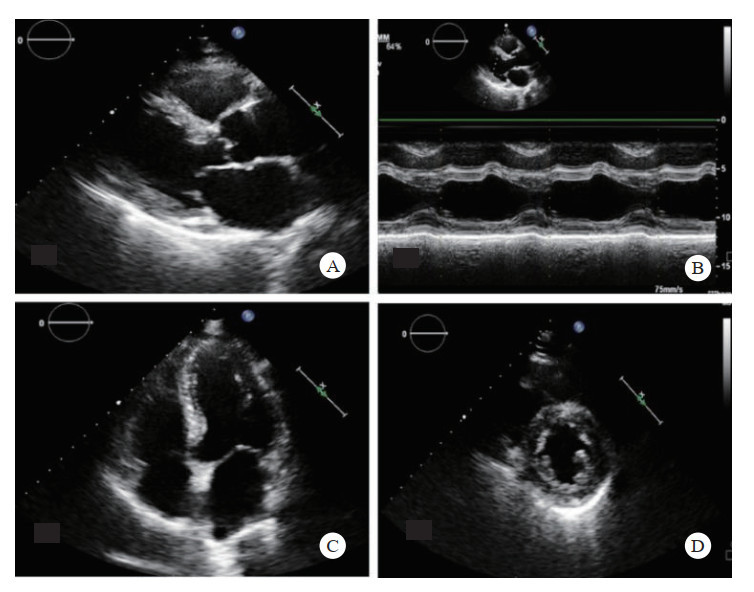

超声快速筛查:目测法观察心腔大小、比例及室壁运动、室壁厚度、心包有无积液,同时快速观察有无血流动力学改变。扫查切面有(图 8):左室长轴切面、心尖四腔心切面、左室M型、左室短轴切面,检查时间不超3 min。

|

| A: 左室长轴切面;B: 左心室M型;C: 四腔心切面;D: 左室短轴切面 图 8 心脏快速检查切面 |

|

|

心包积液为心脏最大舒张期壁层与脏层之间的液性暗区,胸部严重冲击伤时导致心肌出血或心脏破裂,积血在心包内迅速聚积,甚至引起心包压塞。此时航天员可出现呼吸困难、面色苍白、脉搏细弱、血压下降、心音遥远、颈静脉怒张。应立即行心包超声检查,也是休克及急救超声心脏检查的重点部分,方法容易掌握、检查时间短、效果确切。检查切面类似上述心脏快速筛查切面(图 4)。心包积液量的评估见表 1。如确诊大量心包积液后立即可在超声引导下行心包穿刺术,将穿刺针经胸壁刺入心包腔,行减压引流,并确认引流管位置后立即后送。多中心研究证实了超声引导心包穿刺术的安全性[43],纳入研究的各个医疗机构穿刺成功率均较高(91.7%~99%),并发症发生率较低。进针位置多在近心尖部,即锁骨中线外第5~6肋间交界处,检查时间不超2 min。